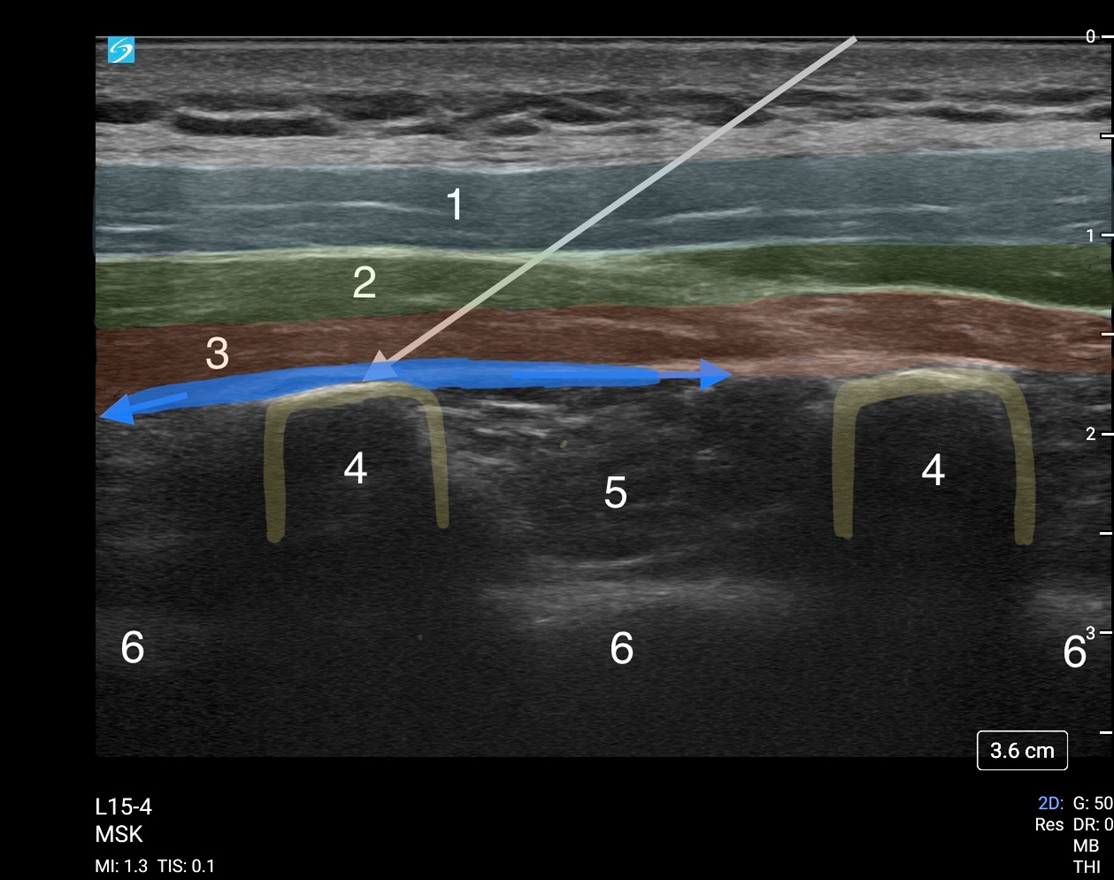

ESP Block Needle Approach Anatomy Image

1. Trapezius Muscle

2. Rhomboid Muscle

3. Erector Spinae Muscle

4. Transverse Process

5. Paravertebral Space

6. Pleura

Arrow - Needle Path

Blue - Local Anesthetic Injection